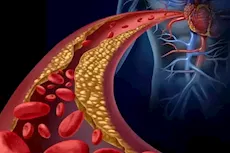

تعد تصبغات الأسنان حالة يتغير فيها لون الأسنان من الخارج، بسبب تراكم المود المختلفة، وكذلك تراكم مادة البلاك، وبقايا الطعام، ونتيجة لغيرها من الأسباب المختلفة.

وأوضح عبد الجواد، أن أعراض تصبغات الأسنان، هو ظهور بقع بنية أو رمادية على الأسنان والضروس، وخاصًة في الجزء السفلي لهما، لافتًا إلى تسبب احراج وإزعاج لمن تنتابه هذه الأعراض.